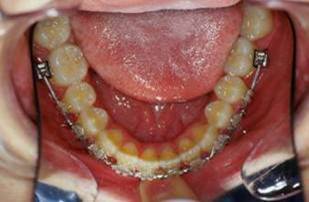

Suite de cas:

J'ai oublie de signaler que depuis RDV 4 une reeducation linguale, au cabinet faite par moi-meme, a commence.

Collage bas fait presque 3 mois apres le haut, avec des elastiques verticaux pendant 3 semaines seulement. Et voici les photos, la suite je vous en passe car il s'agit de simple finition.

Les ponits forts dans cette reeducation sont: maitriser la respiration, reformer le maxillaire, une cooperation extra et une simplicite du system utilise. Merci pour votre attention et a la prochaine... Bonne annee 2007 a tous

P.S. photos au moment du collage bas